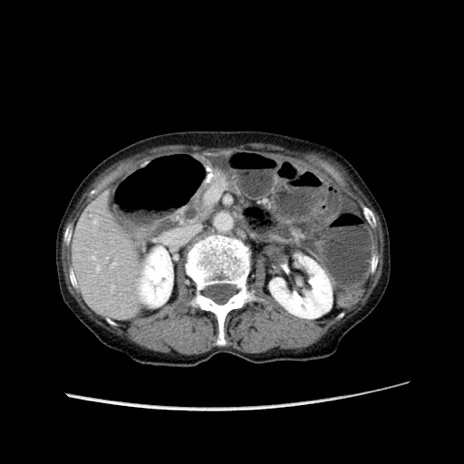

症例25(横断像)

【症例】80歳代女性

【主訴】胸のつかえ感

【現病歴】約9時間前に食後から胸のつかえた感じあり、嘔吐あり、来院。

【既往歴】胃癌(全摘)、胆摘、虫垂炎

【身体所見】心窩部に圧痛あり、反跳痛なし。

【データ】WBC 5700、CRP 0.05